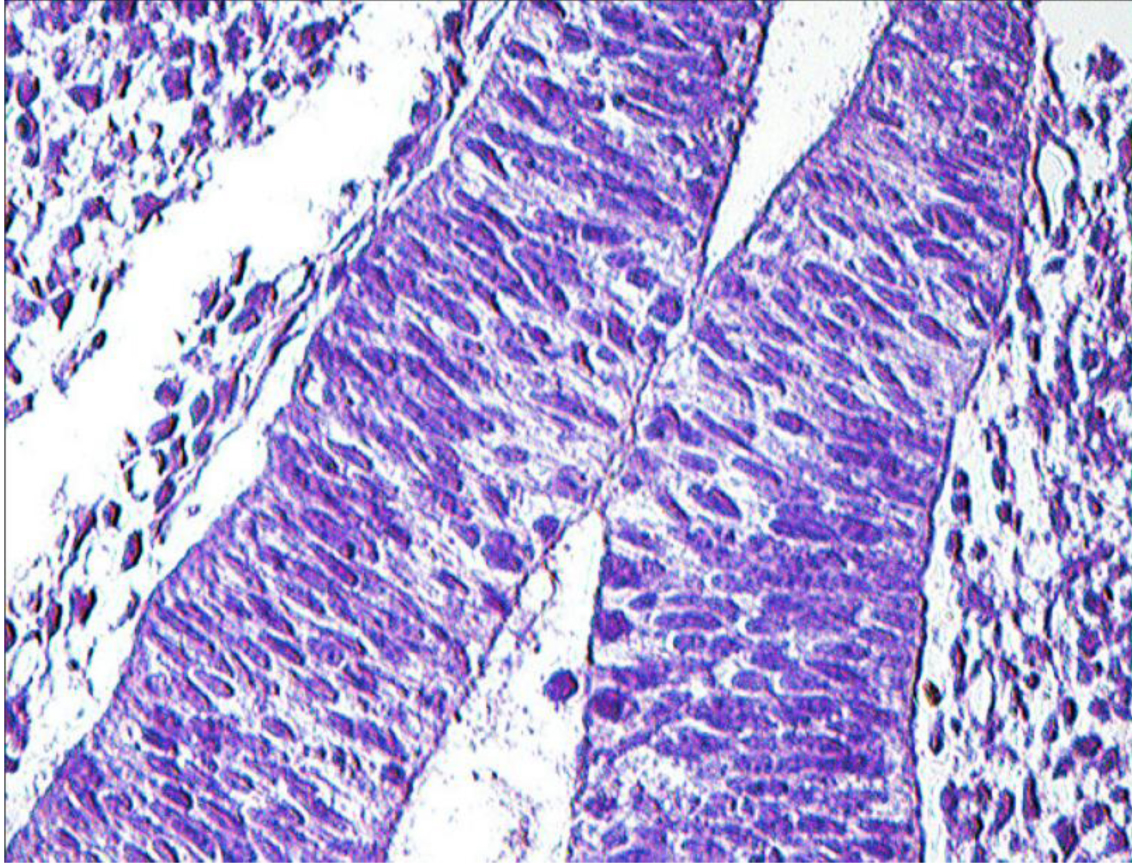

На заключительной стадии сомитного периода (14СК) КР представлен инвагинатом эпителия из полости стомодеума в зоне контакта со стенкой промежуточного мозга. Формирование КР сопровождается трансформацией эпителия из однослойного изоморфного в псевдомногорядный, многорядный мерцательный, многослойный плоский неороговевающий. В этой зоне инициируется процесс М. Наиболее демонстративно М проявляется в области перехода задней стенки КР в эпителий дорзальной стенки глоточной кишки. Дно КР приобретает бокаловидные контуры и обрастает воронку мозга (рис. 3).

Карман Сесселя в гистологическом препарате ограничивает нарастающий пласт многослойного эпителия, который смещается с задней стенки КР на дорзальную стенку глоточной кишки. Перемещение многорядного эпителия по градиенту роста КР сопровождается активизацией апоптоза, пролиферацией клеток в составе пласта и мезенхиме, а также формированием эпителиоцитов качественно новой генерации, потерявших связь с базальной пластинкой эпителия и участвующих в восполнении дефектов в нишах апоптоза (рис. 4).

Эпителий кармана Ратке становится зоной формирования анизоморфных эпителиев глоточной кишки и ее производных. Дискутабельность о судьбе кармана Сесселя [10] сохраняется и по настоящее время, так как анализ гистологического строения эпителия и подлежащей мезенхимы кармана показывает наличие оригинального мезенхимного тяжа, назначение которого не раскрыто. Не исключено его участие в формировании хрящевой основы турецкого седла, в построении прехордальной пластинки либо выполнение роли проводника при возможном разрастании кармана.